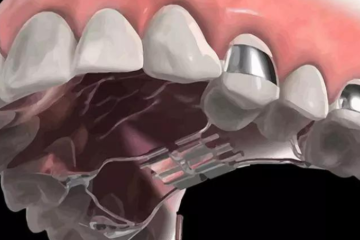

Nong hàm để làm gì? Những lưu ý sau khi nong hàm

Giải đáp thắc mắc: Nong hàm để làm gì? Nong hàm là kỹ thuật giúp nới rộng vòm hàm giúp cho khung hàm cân đối, đủ chỗ để răng di...

Mục đích của kỹ thuật nong hàm là gì? Nong hàm là kỹ thuật nhằm hỗ trợ quá trình chỉnh nha được diễn ra thuận lợi, bằng cách sử dụng...